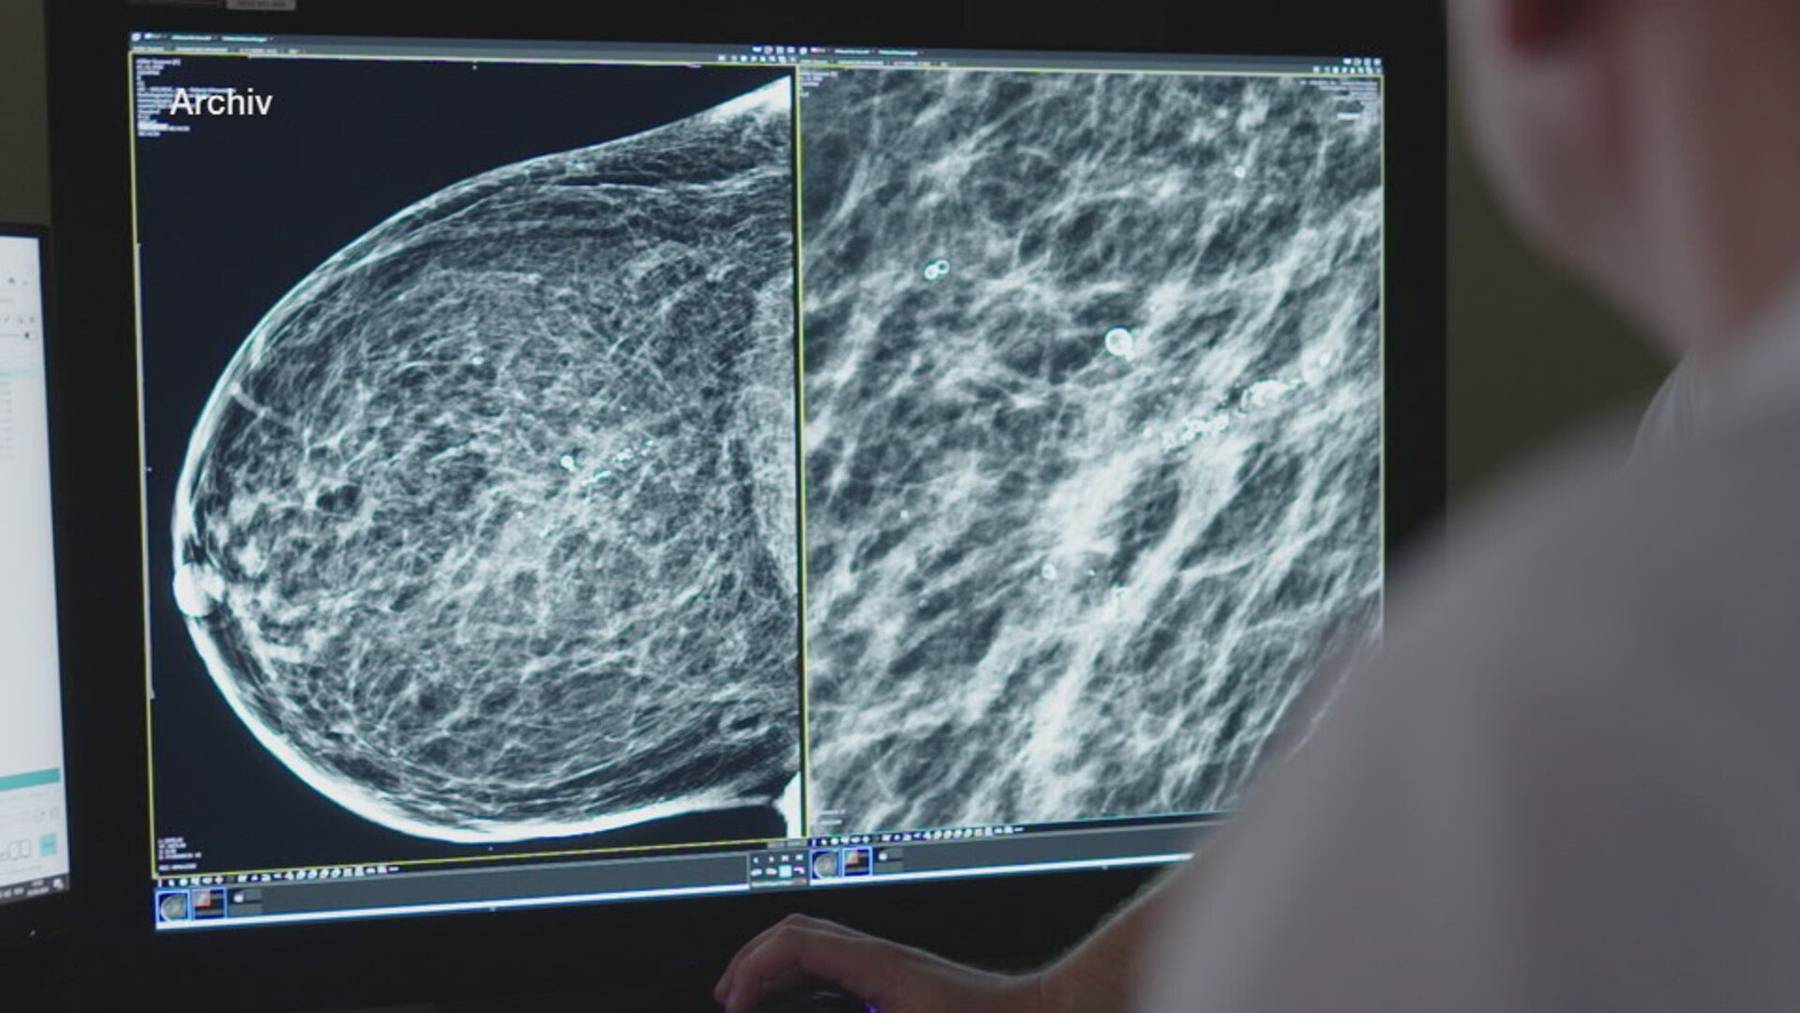

Rita Künstler geht ab 50 regelmässig zur Brustkrebsfrüherkennung. Ihre Brust wird alle zwei Jahre geröntgt. Über mehrere Jahre wird eine auffällige Stelle beobachtet. Letzten Sommer wird ein bösartiger Tumor erkannt. Dank der Früherkennung ist die anschliessende Behandlung weniger belastend: Man kann brusterhaltend operieren, und die Bestrahlung fällt weniger intensiv aus.